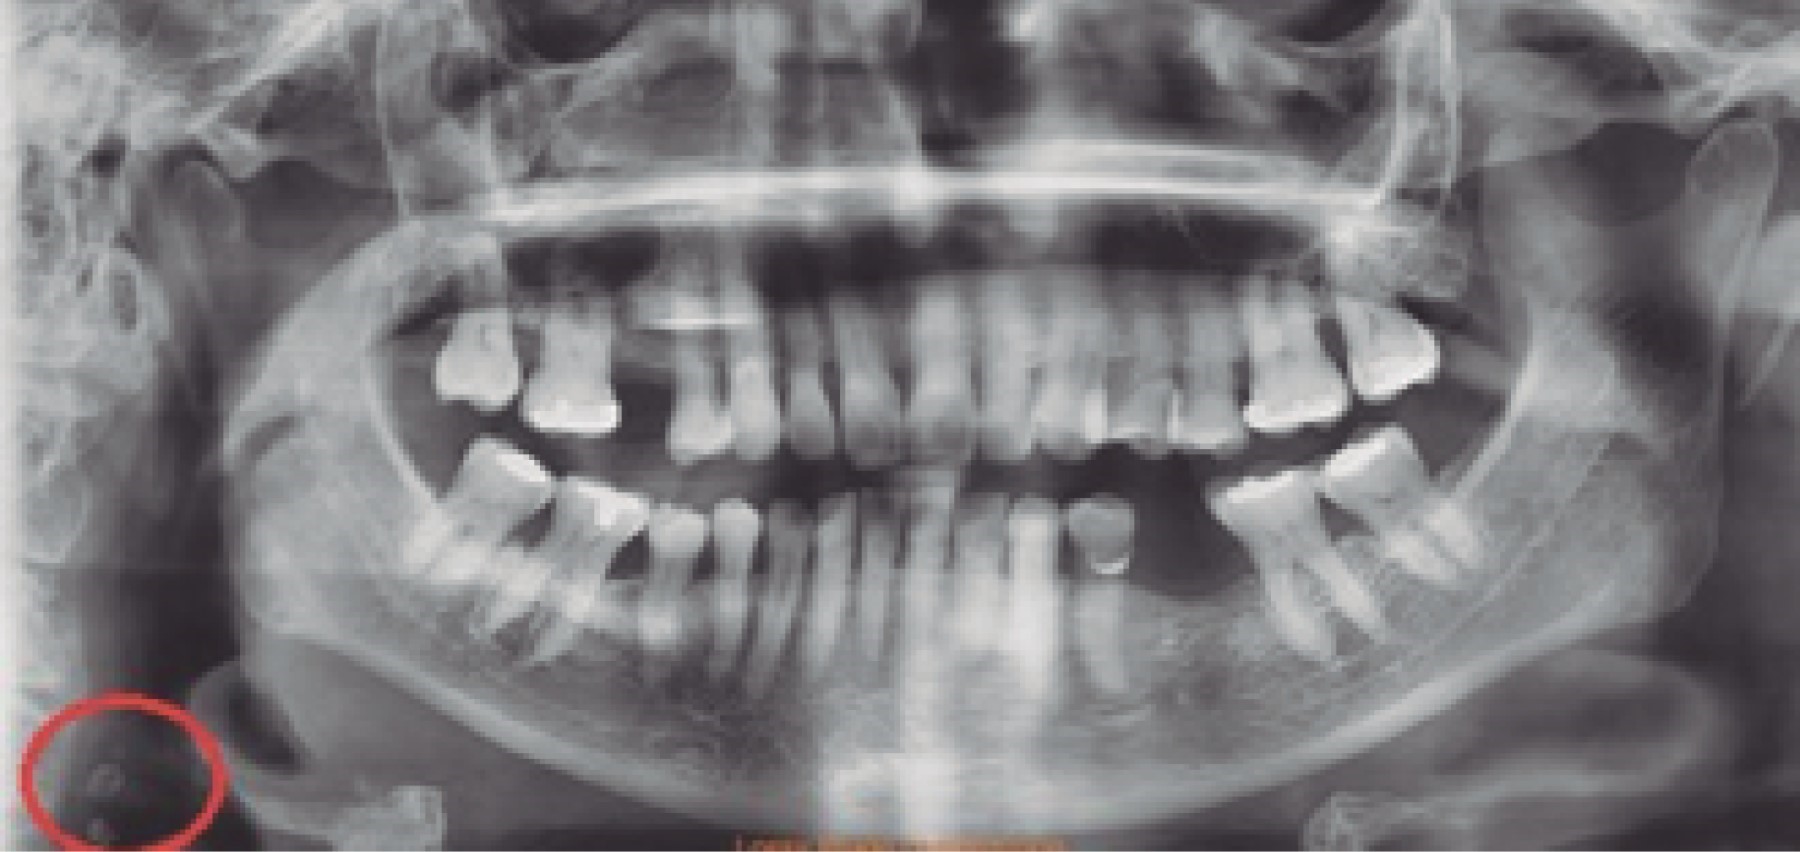

De los 500 pacientes incluidos en este estudio, 336 (67%) pacientes correspondieron al género femenino y 164 (33%) al masculino, con una media de edad de 43 años (mínimo de cinco años y máximo de 91 años con una desviación estándar de 20.7). En 239 (47%) pacientes no se observaron alteraciones. Los principales hallazgos fueron los siguientes: 226 (45%) casos con pérdida ósea de proceso alveolar, seguido de hallazgos radiográficos sugestivos de alteración en la zona articular (ATM) con 171 (34%) casos; en 151 (30%) casos se observaron signos radiográficos de calcificación del ligamento estilohioideo (CLE-síndrome de Eagle) (Figura 1); 18 (3%) casos presentaron estructuras correspondientes a calcificación de carótida (CC) y en 11 (2%) casos se localizaron zonas radiolúcidas semejantes a lesiones quísticas (Figura 2). Los hallazgos se reportan en la Tabla 1.

Respecto a la muestra de CLE (Figura 3), el expediente clínico de 51 pacientes indica que presentaron síntomas relacionados con síndrome de Eagle (SE), mismos que se describen en la Figura 4. Otras de las patologías encontradas fueron las calcificaciones de la carótida en 18 casos (Figura 5), sin que se asociaran con alguna manifestación clínica, o hubieran sido detectadas en el expediente clínico.7,8